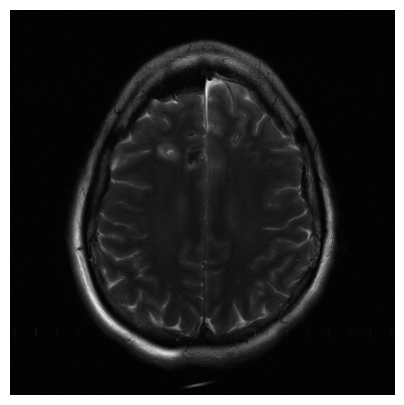

Qualitative.

The visual inspection of the images reconstructed (available in Fig. 2) at acceleration factor 4 shows little to no visible difference with the ground truth original image. However, when increasing the acceleration factor to 8, we can see that smoothing starts to appear which leads to a loss of structure as can be seen in Fig. 3.

| T1 PSNR: 41.56 SSIM: 0.9506 | T2 PSNR: 40.68 SSIM: 0.9554 | FLAIR PSNR: 39.60 SSIM: 0.9321 | T1POST PSNR: 42.53 SSIM: 0.9683 |